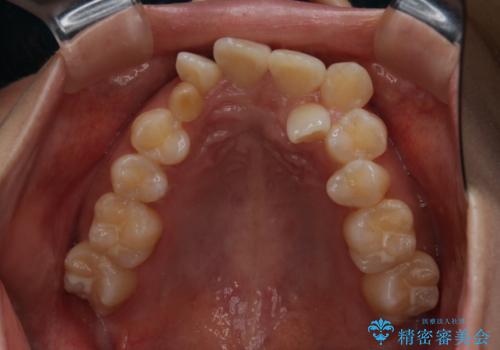

がたつきが強いガチャ歯。埋伏歯抜歯+矯正。すごいところに犬歯が埋まっていたのを抜いてワイヤー矯正治療

- 歯のがたつきを主訴に来院されました。

がたつきの強さから4本抜歯の必要性がありましたが、右上の歯は犬歯が一本埋まっており、乳歯がある状態でした。

当初、犬歯が動くようであれば代わりに小臼歯を抜歯する予定でしたが、

開窓して器具で力をかけても動く様子がなかったため抜歯とし、小臼歯を犬歯に見立てて治療を完了しました。